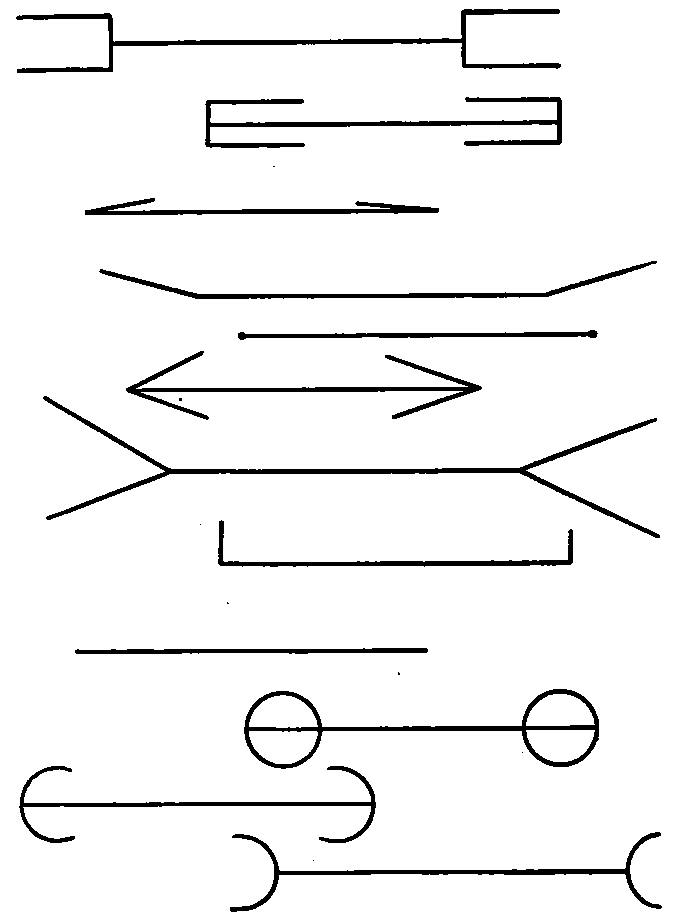

| 23. | Normal diaphragm curve in normal breathing | 577 |

| 24. | Curve in diaphragm before and during talking by a stutterer | 577 |